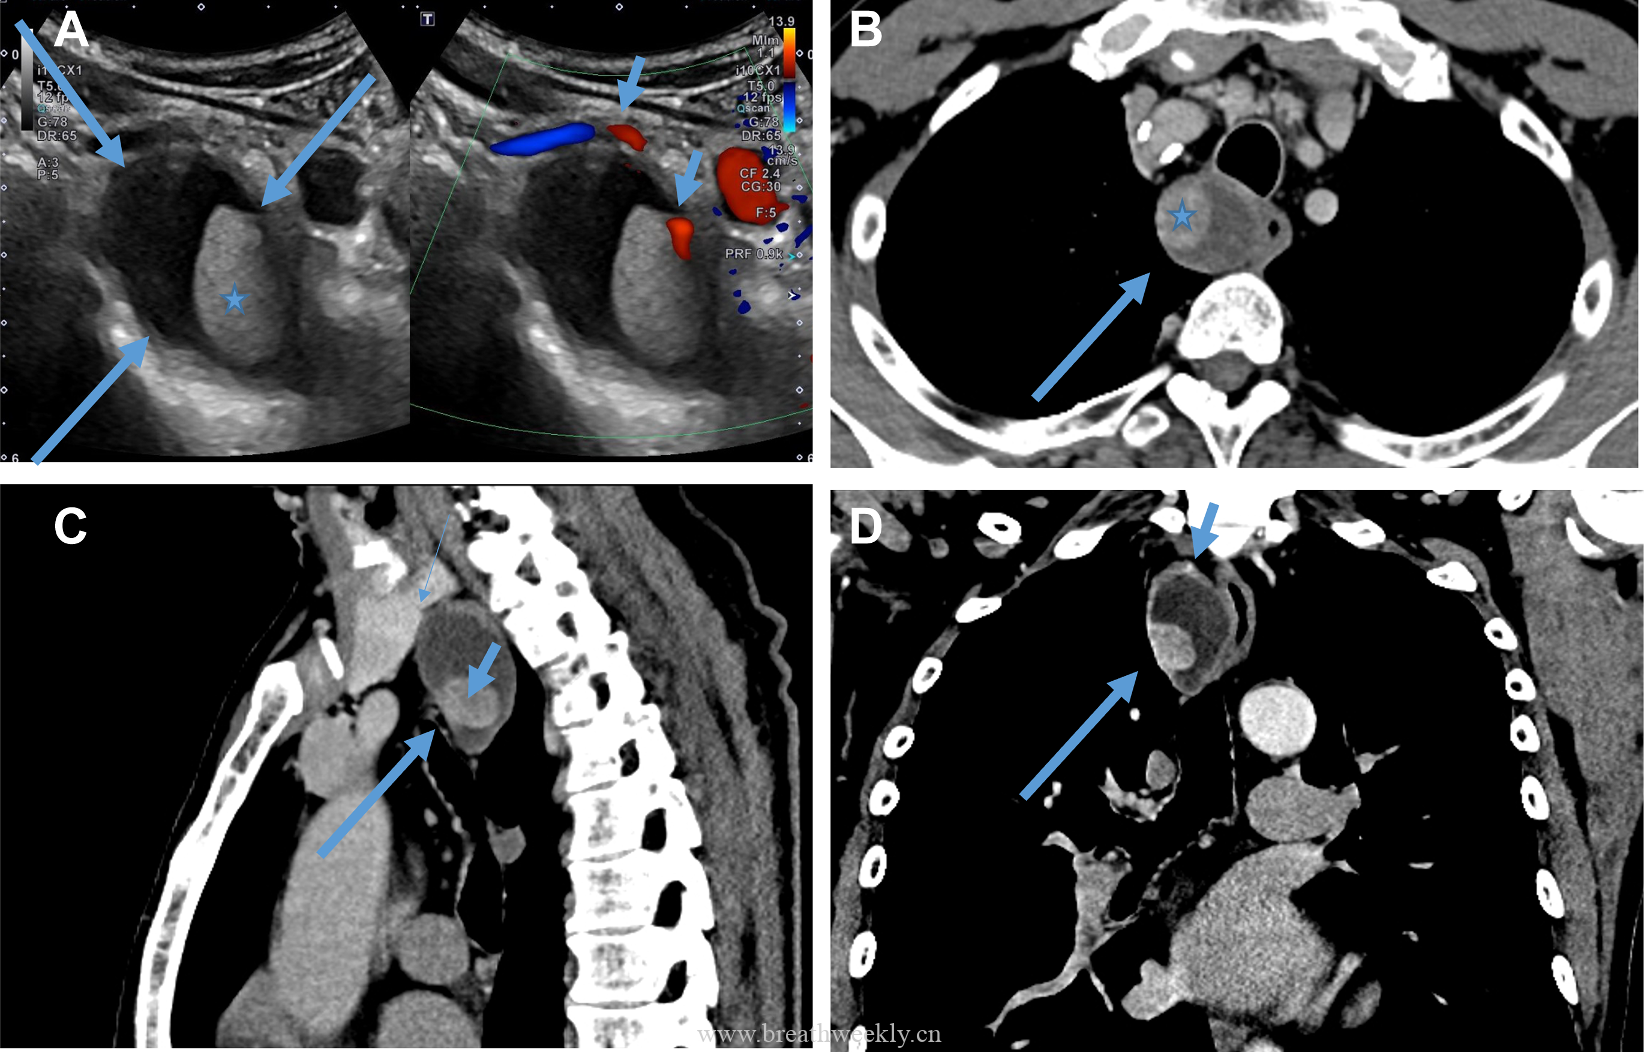

病例61六六4年前更新关注私信042770 该病例由付甜提供 网页端网页端直接点击查看结果 公众号内回复“病例61”查看结果 小程序点击底部 文章附件内的资源下载可显示结果 © 版权声明文章版权归作者所有,未经允许请勿转载。THE END每周病例病例库经典病例# 肺曲霉病 喜欢就支持一下吧点赞0 分享QQ空间微博QQ好友海报分享复制链接收藏